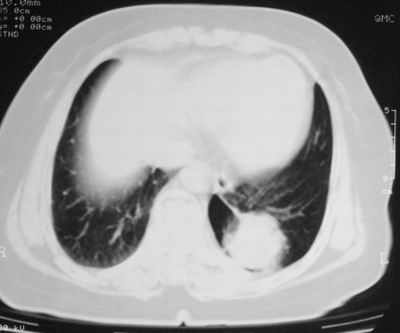

患者,女,64岁,4年前左腮腺"多形性"腺瘤手术治疗史.现复查胸部ct见左下肺块状影,该影与原左腮腺手术是否有联系?

本次复查胸部ct

左下肺软组织块影,有分叶、毛刺、空泡及胸膜牵拉征,左下肺周围性肺癌。

左肺下叶周围型肺癌,支持!(软组织肿块+分叶+毛刺+空泡+胸膜凹陷征)

左下肺软组织密度影,可见分叶,边缘可见毛刺征,胸膜增厚,强烈要求左下肺周围型肺癌

左下肺后基底段实性肿块,周围有毛刺,病变周围有肺气肿,与降主动脉间有条带状影相连,病灶4年前查体发现,纵隔内未见肿大淋巴结。考虑.肺隔离症,建议增强扫描与周围型肺癌鉴别。